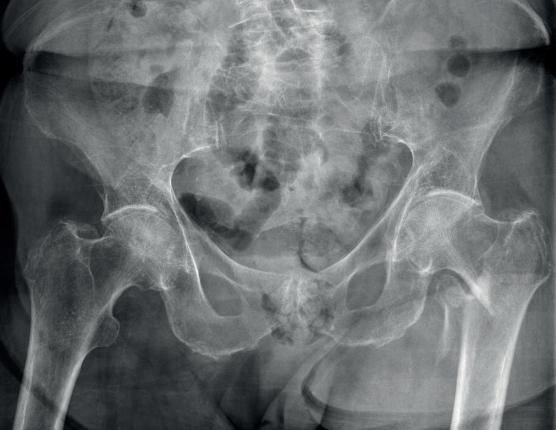

De hoftenære frakturer inddeles efter fire anatomiske områder: caput femoris, collum femoris, pertrokantær og subtrokantære (figur 21.2). Derudover kan de grupperes i intrakapsulære frakturer (caput og collum femoris) og ekstrakapsulære frakturer (pertrokantære og subtrokantære) grundet deres beliggenhed ift. femur-

kapslen. Det har afgørende betydning for behandling og prognose, da de intrakapsulære frakturer kan ødelægge blodforsyningen til caput femoris og dermed medføre avaskulær nekrose (figur 21.3).

Incidensen har i mange år været faldende, men er de sidste år steget og ligger på omkring 1,2 per 1.000 indbyggere per år for personer over 65 år. Det svarer til ca. 7.000 frakturer årligt hos de over 65-årige. Stort set alle hoftenære lårbensfrakturer (caput femoris er ikke med i denne definition) hos de ældre er osteoporotiske lavenergifrakturer, hvor incidensen er stærkt stigende efter 50-årsalderen. Hoftenære frakturer hos yngre kræver ofte høj energi, men man bør altid have mistanken om en osteoporoserelateret fraktur – selv hos yngre patienter.

Klinisk ses ofte, men ikke altid, et oprykket og udadroteret ben hos patienten med en hoftenær fraktur (figur 21.4). De kan typisk ikke støtte på benet. De har stærke smerter, der forværres ved passiv rotation af hoften. Patienter med en indkilet fraktur eller fissur kan dog ofte støtte eller løfte benet fra lejet, men det kliniske billede domineres af de stilleliggende patienter.

Der skal på mistanken om en hoftenær fraktur tages røntgen af bækken samt den afficerede hofte. Frakturen er oftest let at erkende på røntgen, men kan man ikke se en fraktur, og er der fortsat klinisk mistanke, bør der foretages en MR-skanning, alternativt en CT-skanning for afklaring, før patienten mobiliseres. De klassiske differentialdiagnoser er ramusfraktur, acetabulumfraktur, luksation af total hoftealloplastik (typisk dog indadroteret ben = bageste luksation af hofteprotesens ledhoved) og periprostetisk fraktur. Ved mistanke om caput femorisfraktur bør der altid foretages en CT-skanning.